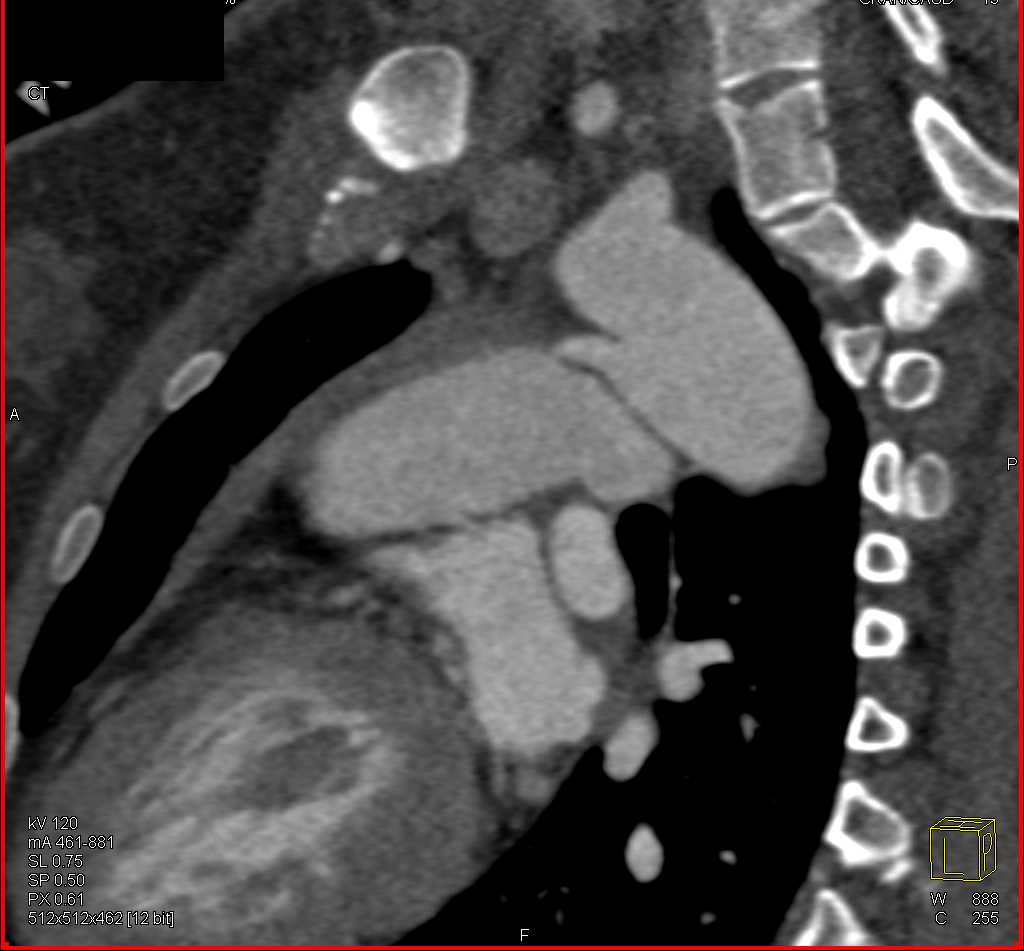

Gunshot Wound (GSW) Thigh Without Vascular Injury